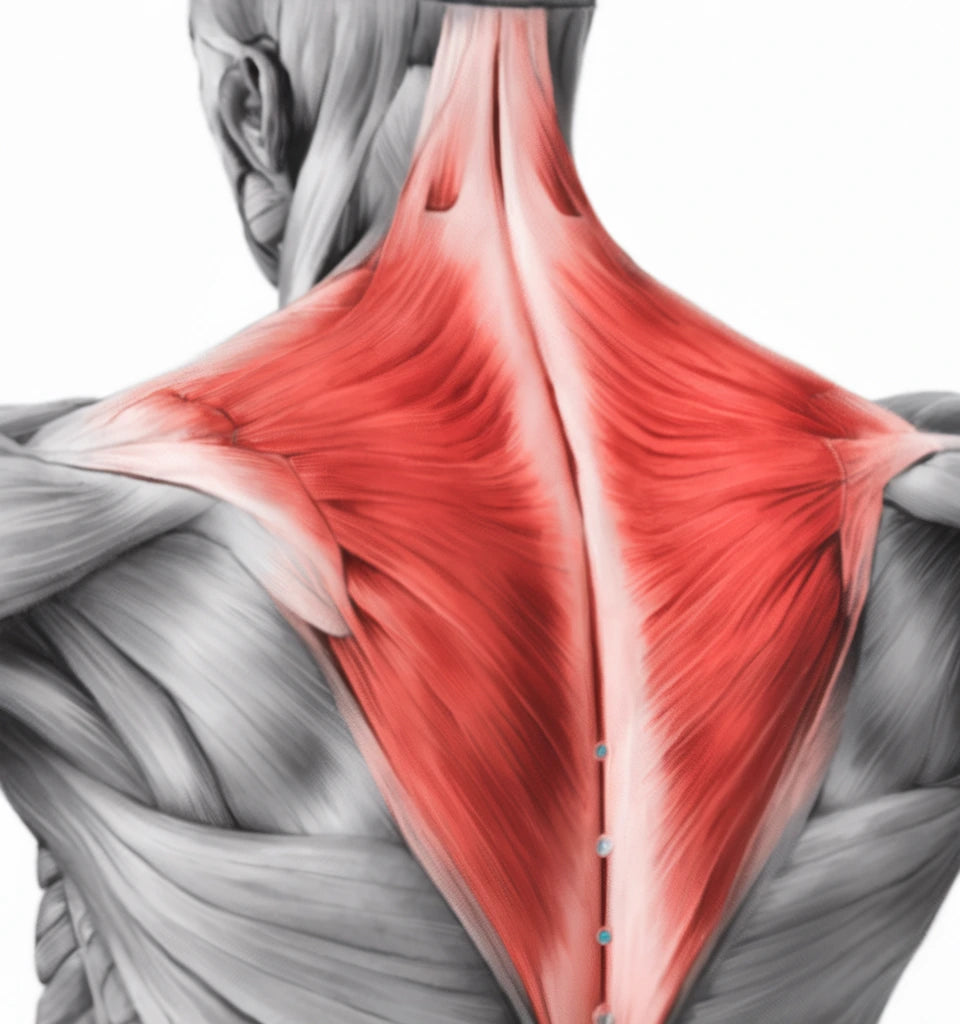

Axelleden är en av kroppens mest rörliga leder – men också en av de mest utsatta. Smärta i axeln kan bero på inflammation, överansträngning eller ledförslitning. Lär dig mer om olika axelproblem och hur du kan lindra dina symtom.